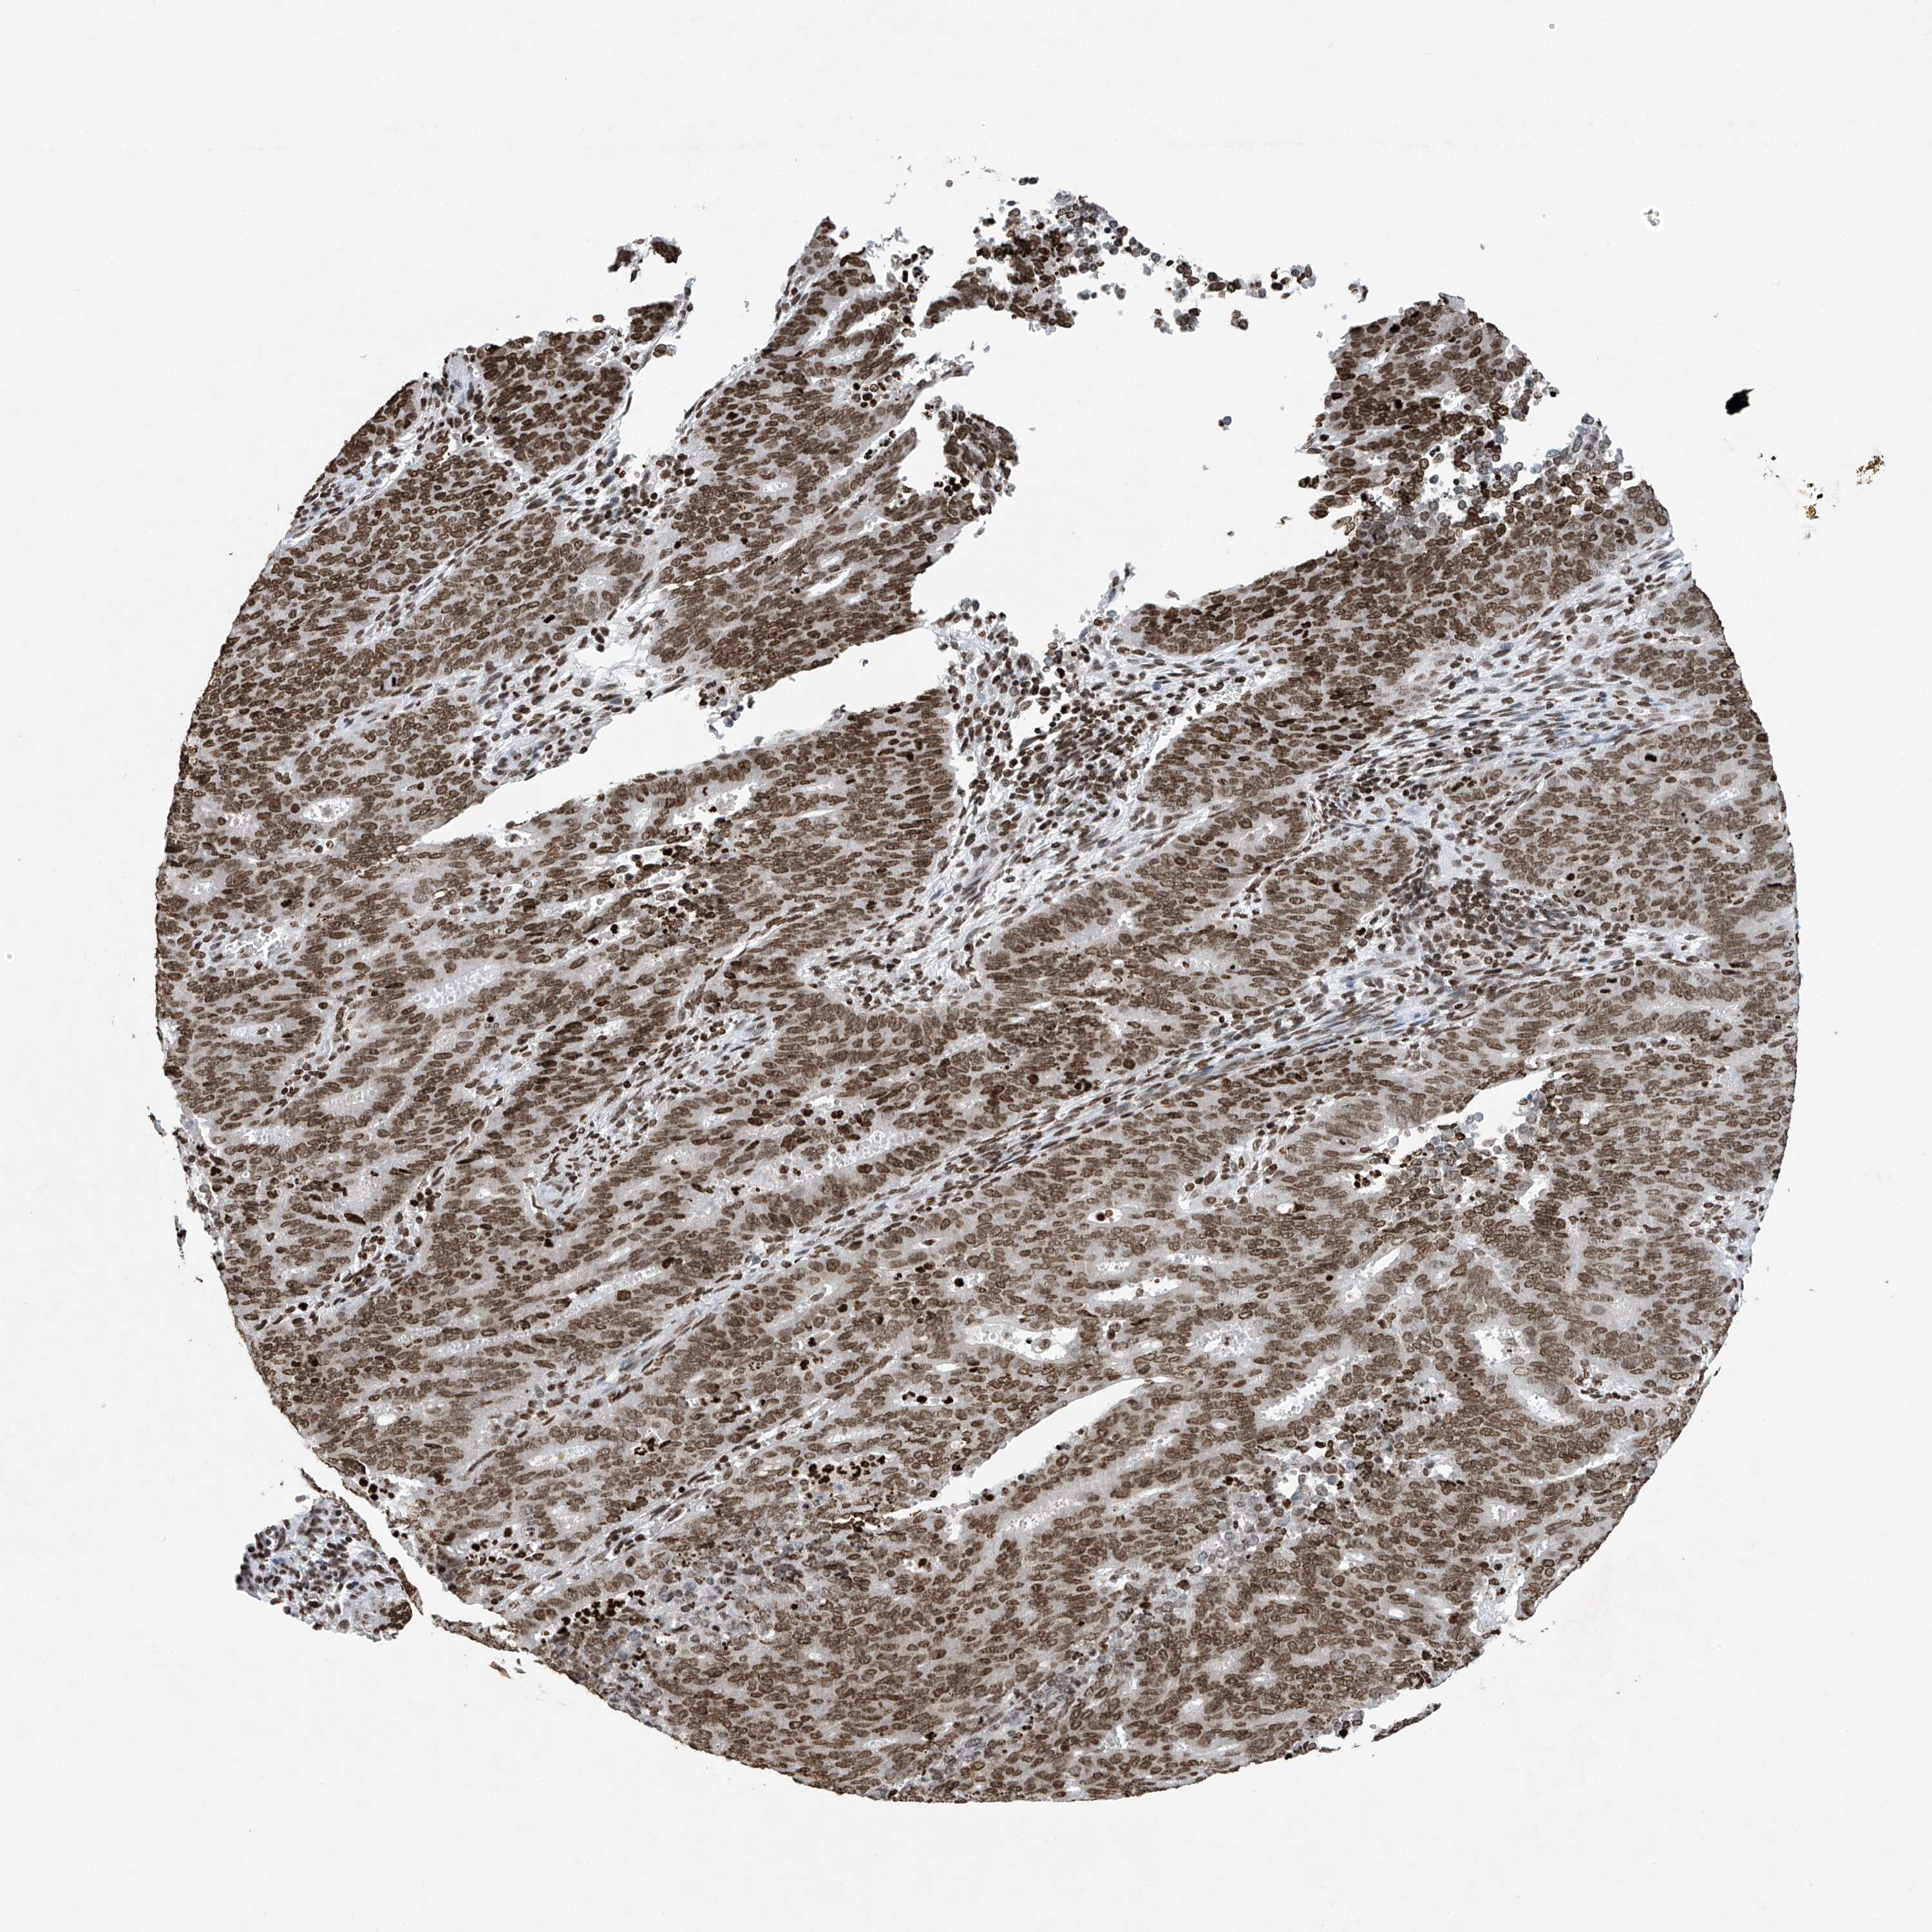

CERVICAL CANCER - Protein expressioni

A mouse-over function shows sample information and annotation data. Click on an image to view it in a full screen mode. Samples can be filtered based on level of antibody staining by selecting one or several of the following categories: high, medium, low and not detected. The assay and annotation is described here.

Note that samples used for immunohistochemistry by the Human Protein Atlas do not correspond to samples in the TCGA dataset.

Antibody stainingi

Antibody staining in the annotated cell types in the current human tissue is reported as not detected, low, medium, or high, based on conventional immunohistochemistry profiling in selected tissues. This score is based on the combination of the staining intensity and fraction of stained cells.

Each image is clickable and will lead to virtual microscopy that enables deeper exploration of all samples and also displays staining intensity scores, fraction scores and subcellular localization as well as patient and tissue information for each sample.

Antibody HPA042201

Antibody CAB011503

Antibody CAB037279

Squamous cell carcinoma, NOS

Adenocarcinoma, NOS